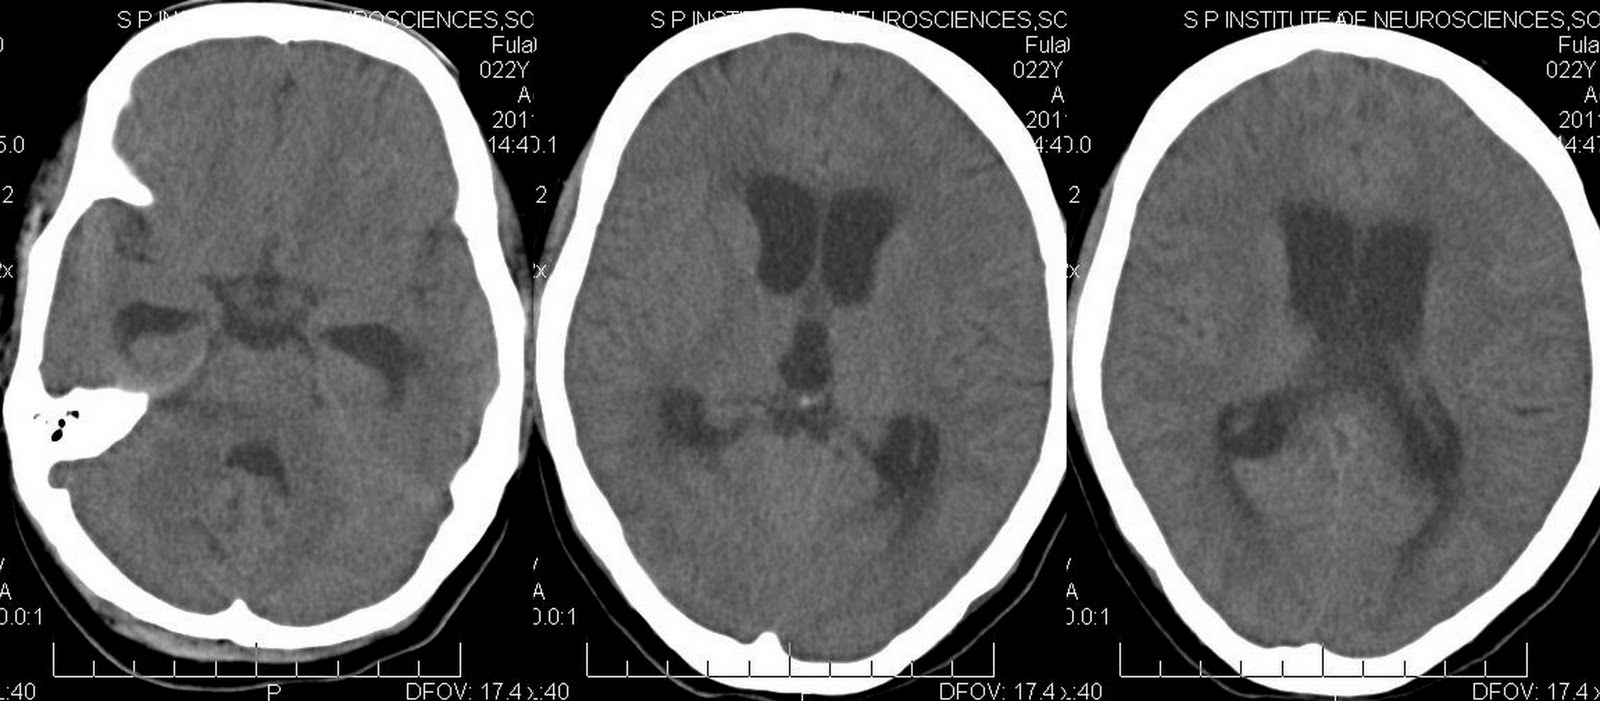

Bacterial Meningitis CT Scan Ct Scan Meningitis more patients with meningitis are undergoing ct and the number of inappropriate requests are increasing. computed tomography (ct) should be performed in patients with impairment of consciousness and/or. Your doctor will flex your leg at the knee and. computerized tomography (ct) or magnetic resonance imaging (mri) scans of the head may show swelling or. leptomeningitis, which. Ct Scan Meningitis.

Head CT on day 2 for evaluation of meningitis. (a) Axial head CT shows... Download Scientific Ct Scan Meningitis more patients with meningitis are undergoing ct and the number of inappropriate requests are increasing. leptomeningitis, which is more commonly referred to as meningitis, represents inflammation of the subarachnoid space (i.e. sometimes meningitis is due the direct spread of infection from paranasal sinus or mastoid infection, thus imaging helps exclude this source of infection. mri is. Ct Scan Meningitis.

e Axial noncontrast head CT demonstrates enlargement of the lateral... Download Scientific Diagram Ct Scan Meningitis Your doctor will flex your leg at the knee and. more patients with meningitis are undergoing ct and the number of inappropriate requests are increasing. mri is superior to ct scanning in the evaluation of patients with suspected meningitis, as well as in demonstrating leptomeningeal. leptomeningitis, which is more commonly referred to as meningitis, represents inflammation of. Ct Scan Meningitis.